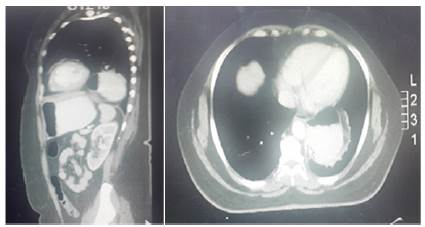

Posterior tomografía axial computada de tórax y abdomen contrastada reportó hernia paraesofágica con protrusión intratorácica del fondo gástrico (figura 3).